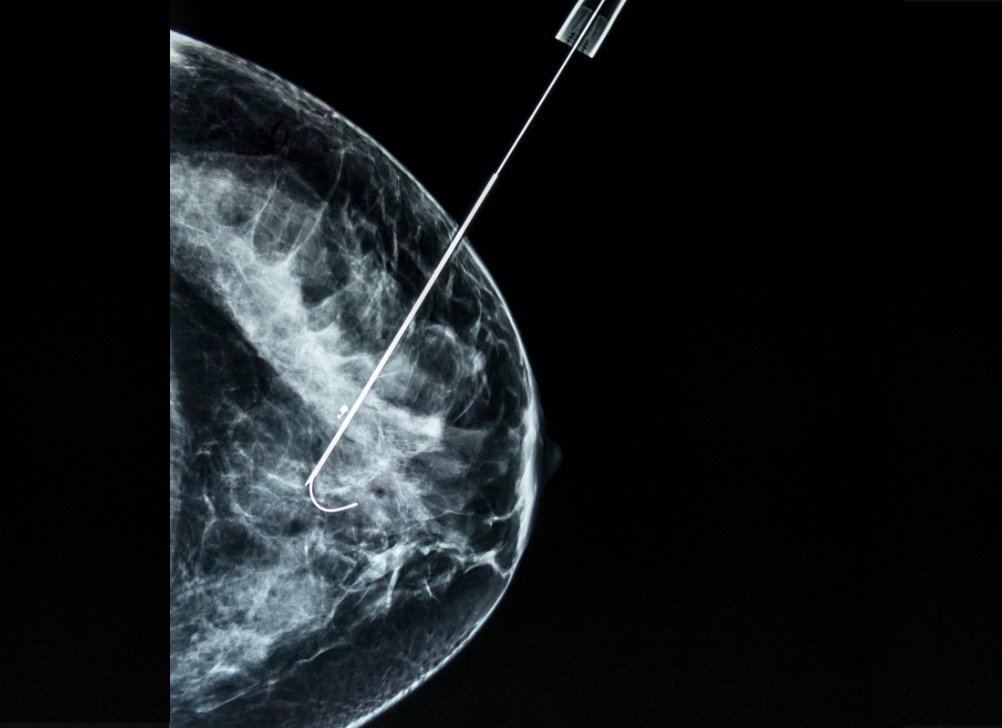

- получение ложноотрицательного результата биопсии из-за того, что ткань была взята не из опухоли, а из области рядом с опухолью (то есть промах, если говорить как есть);

- получение большего количества столбиков ткани при биопсии, особенно в случае подозрительных на опухоль новообразований небольшого размера. В рамках здравого смысла конечно же. Естественно, нет никакого смысла в получении пятнадцати столбиков, но получить 5-7 столбиков ткани порой имеет смысл. При взятии двух-трех столбиков ткани существует риск “промахнуться”.